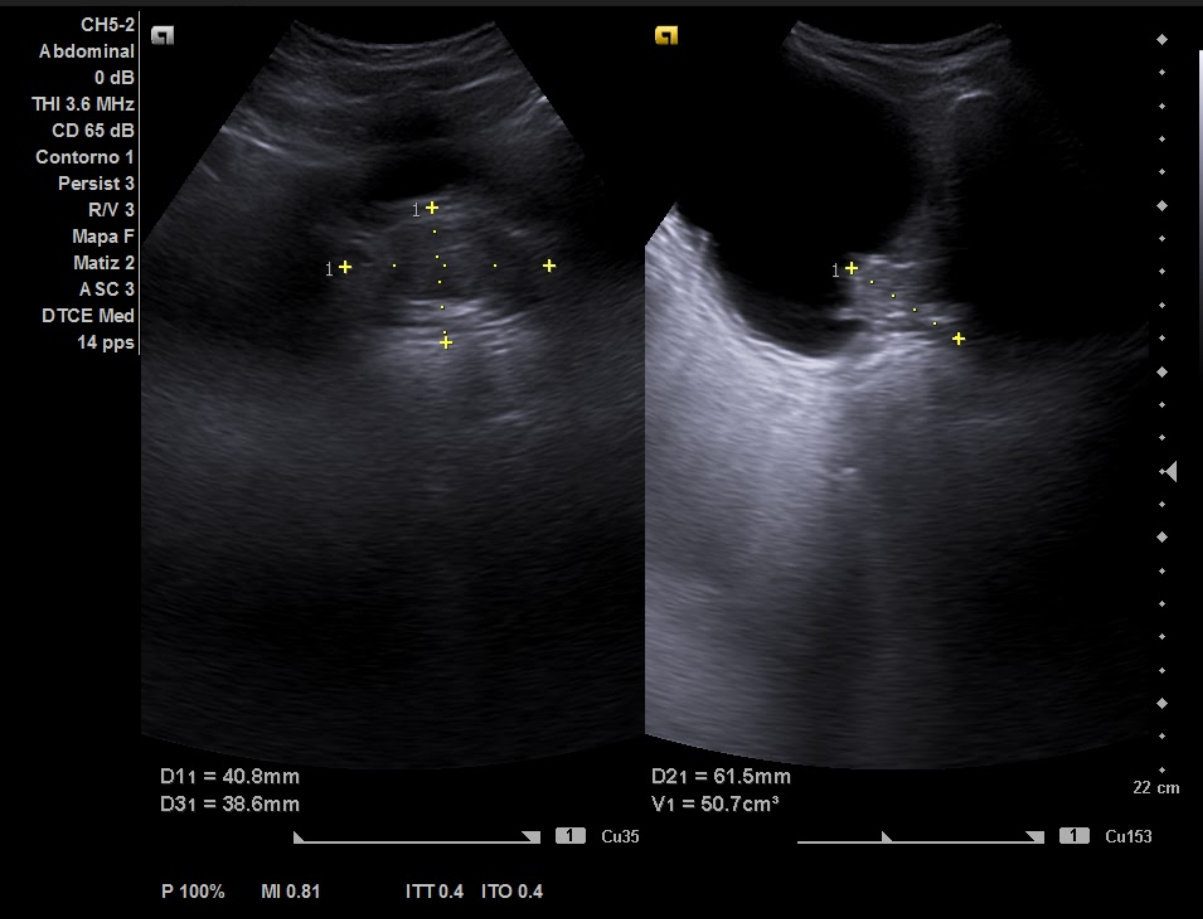

Hallazgos ecográficos

Ecografía aparato urinario en Centro de Salud: Riñones de tamaño normal, parénquima conservado con dilatación pielocalicial grado II-III izquierdo y grado II derecho. Vejiga con aspecto trabeculado, pared irregular con divertículos. Volumen premiccional 550 cc, postmiccional 450 cc. Volumen prostático de 50 cc.